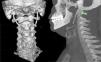

Varón de 57 años, sin antecedentes personales de interés; acude a las consultas de Otorrinolaringología por cuadro de disfagia orofaríngea y sensación de cuerpo extraño cada vez más acentuada. La exploración física y nasofibrolaringoscópica es anodina, por lo que realizamos un estudio de extensión con tomografía computarizada de cuello, que muestra una elongación de ambas apófisis estiloides de 5cm en el lado izquierdo y 7cm en el derecho (fig. 1), diagnosticando al paciente de síndrome de Eagle. Dada la evolución y la progresión de la clínica, decidimos intervenir al enfermo de resección de ambas apófisis estiloides y astas posteriores del hioides (figs. 2 y 3). El paciente presentó una evolución satisfactoria tras la intervención.